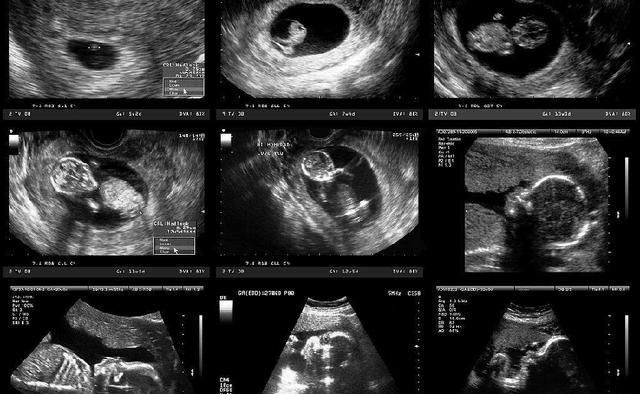

怀孕的过程虽然很漫长,但被很多人看作是很幸福的时光,慢慢感受着一个小生命在自己的身体中成长给人带来满足感,可是你真的知道宝宝在你腹中是如何成长的吗?想不想知道现在他是什么样子的呢?

生命的源头来自于精子和卵子结合成的受精卵。女性会大概在经前14天排卵,如果这段时间精子能够进入输卵管腔的话,24h之内受精卵就可以形成,受精后大概一周的时间受精卵就能在子宫内膜着床。

医生会从准妈妈的末次月经开始算妊娠期,会比受精卵形成的时间早2周,从这个时候开始算整个妊娠的过程,共40周。

妊娠4周时,孕妇的子宫还没有发生明显的变化,胎儿目前还是胚胎,已经有胎盘和体蒂了;

妊娠8周时,准妈妈应该已经可以感受到早孕反应了,胎儿也已成胎形,头部、身体、四肢都能看得出来,心脏和大脑也已经开始发育;

妊娠12周时,各位准妈妈大多发现自己变胖了吧,不仅重量增加,连腰围也增加了,此时胎儿已经具备人形,很多器官已开始工作和发育;

16周时,肚子是不是已经鼓起了呢,乳房也会变涨,而胎儿身长大约16cm,肺部开始工作了,四肢已经发育完成,可以做出不少动作了因此准妈妈也可以感受到胎动;

20周时,这段时间大家应该是比较轻松的,吃的不少,也不容易恶心,行动也比较方便,胎儿也长到了25厘米左右,开始出现体脂,也开始生长毛发,并且他的感官也开始飞速发育;

24周时,由于腹部愈发鼓了,孕妇的体态也和之前有了很大差别,行动时重心会向后移动,此时的胎儿身长大概30厘米,大脑也在迅速发育,脂肪开始变厚,不过皮肤仍旧是薄薄的,而细小支气管和肺泡也在慢慢发育。

28周时,已经进入孕晚期了,准妈妈们也会感受到腰酸背痛,而宝宝发育到了大概35厘米,也正在努力沉积脂肪和进行呼吸运动,他的眼睛也能够闭合、睁开了。

32周时,准妈妈这这段时间运动也开始变得迟缓,能感受到背部、大腿的疼痛,要注意休息,胎儿看起来也很像刚出生的宝宝了,各器官发育接近成熟。

36周时,准妈妈的体重目前已是巅峰,腹部非常大有很沉重,肚脐也是外凸的样子,能感受到腹部下坠感,这周结束宝宝就能称为足月儿了。

40周时,准妈妈要随时准备生产了,此刻宝宝已经发育成熟,身长大约50厘米,生存能力也比较强了。

以上就是胎儿在孕妈肚子里的发育过程,你都清楚了吗?